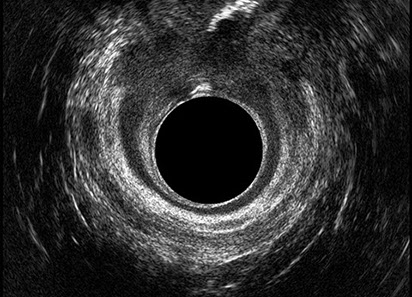

L’ecografia transanale è un esame diagnostico per immagini che consiste nell’introduzione di un trasduttore ad ultrasuoni. Le immagini qualitativamente migliori del canale anale sono ottenute usando un trasduttore rotante, montato in un manipolo rigido, che fornisce un’immagine a 360°. Con le apparecchiature più moderne è anche possibile ottenere immagini tridimensionali.

L’ecografia transanale permette di distinguere la sottomucosa che riveste il canale anale, lo sfintere anale interno, e lo sfintere anale esterno.

Proctal dispone di apparecchiatura per ecografia endoanale 3D con sonda rotante.